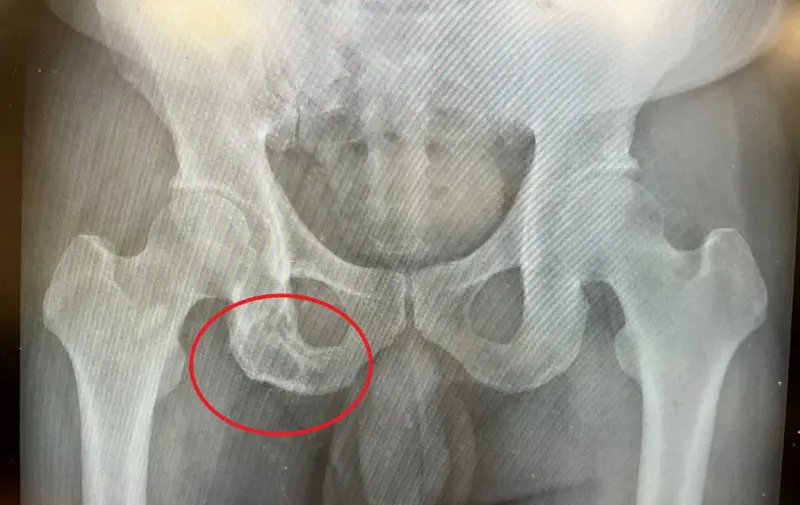

台中慈濟醫院血液腫瘤科主治醫師黃冠博說,白先生最初認為工作勞累導致臀部疼痛,僅進行復健和民俗整復,痛到無法忍受才就醫,電腦斷層檢查發現坐骨骨頭有被侵蝕的病灶,轉診至本院,抽血檢驗多項腫瘤指數都是正常,懷疑疾病不單純,於是進一步做血液蛋白質免疫電泳分析。

結果顯示,白先生血清中的單株球蛋白濃度異常升高,再經由骨髓切片檢查,確診為「多發性骨髓瘤」造成的骨骼病變,並患有單株丙型免疫球蛋白血症。